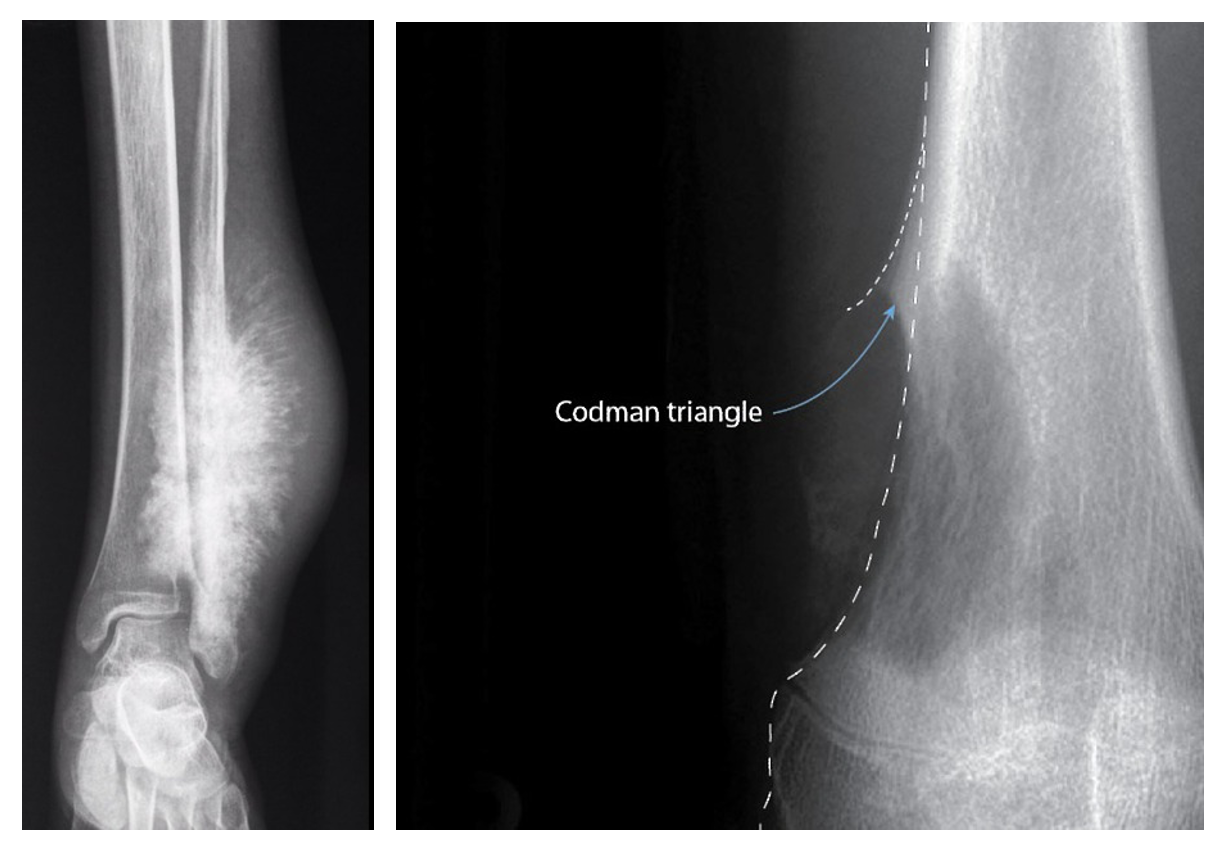

• Codman 삼각형 (Codman's triangle): 골막이 종양에 의해 들어 올려지면서 나타나는 삼각형 모양의 골막 반응

• Sunburst 양상 (Sunburst appearance): 종양에 의해 생성된 골침(spicule)이 뼈 표면에서 방사상으로 뻗어나가는 모양